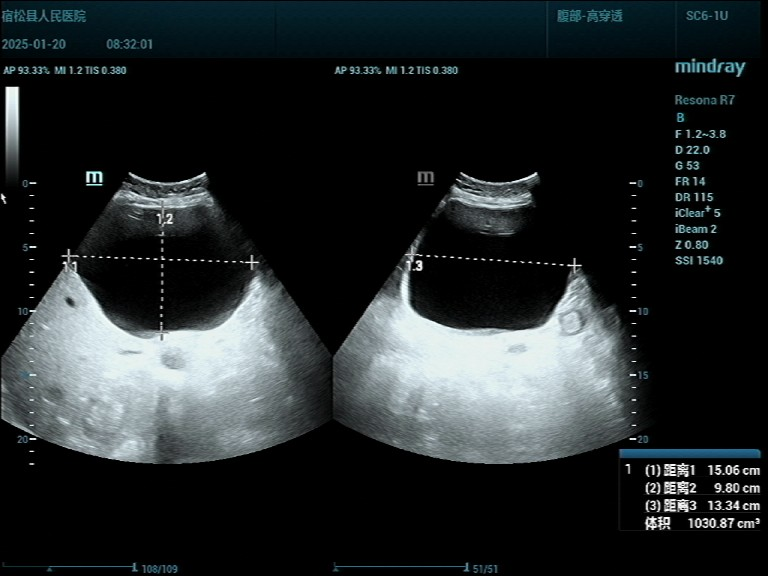

上腹部彩超:显示肝脏多发性囊肿,肝左叶最大囊肿已达151*133*98mm(体积:约1030ml),足足有一个西兰花那么大。巨大的肝囊肿压迫了周围组织结构,引起患者上腹部不适症状,并严重影响其生活。如果不及时处理,囊肿可能继续增大,遇外力挤压导致破裂出血,甚至可能危及患者生命,治疗迫在眉睫。

▲1.治疗前超声显示 ▲2.穿刺针经皮肝进入囊肿内